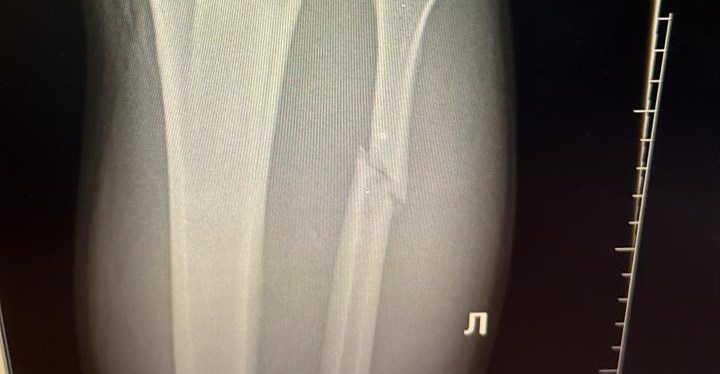

Walker reveló el martes que se rompió el peroné izquierdo, cortesía de una patada en la pantorrilla de Sutherland al comienzo de la pelea. Aún así logró derribar a su oponente al suelo y obligarlo a someterse.

Según el brasileño, que ya ha ganado cuatro seguidos en la UFC, necesitará una “fuerte recuperación” durante cinco a seis semanas.